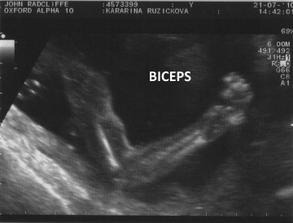

Naše šťastíčko